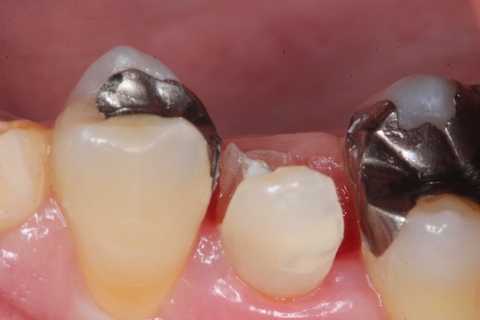

今日の充填治療55(遠心隣接面カリエス) 2023.12.21